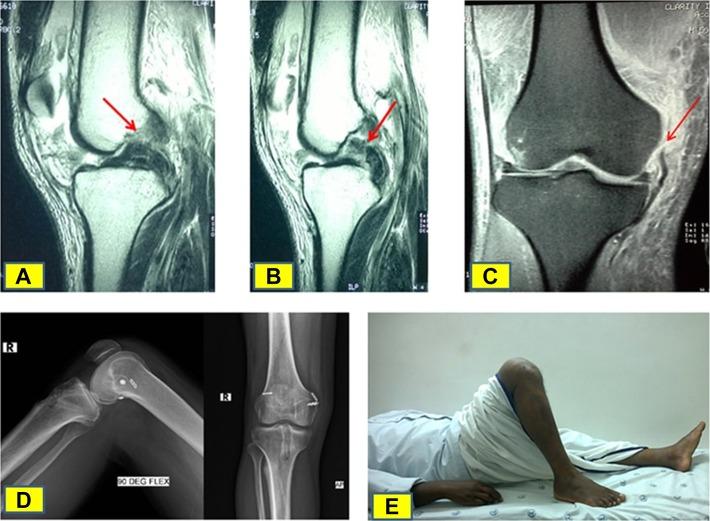

The knee dislocation-3 (KD3) injury pattern is the most common form of multiligamentous injury. Medial KD3 (KD3-M) and lateral KD3 (KD3-L) are 2 anatomically different varieties of this injury.

A cohort of 45 patients with multiligamentous knee injuries (31 KD3-M, 14 KD3-L) who were operated on between 2011 and 2015 were compared. The cruciate ligaments were reconstructed, and the collateral ligaments were managed either conservatively or surgically depending on intraoperative laxity, tissue condition, injury site, and chronicity. The mean follow-up was 36 months (range, 24-72 months). The International Knee Documentation Committee (IKDC) score, Lysholm score, knee flexion range of motion (ROM), and laxity on stress radiographs were compared. Various factors likely to influence the outcomes were also analyzed.

The mean IKDC score, Lysholm score, and knee flexion ROM for the 45 patients were 74.74, 87.66, and 126.78°, respectively. There was no significant difference between the KD3-M and KD3-L groups in terms of the postoperative IKDC score ( = .768), Lysholm score ( = .689), knee flexion ROM ( = .798), and laxity on stress radiographs ( = .011). Patients with a transient dislocation had better outcomes (76.51, 89.41, and 128.61°, respectively) than those with a frank dislocation (67.62, 80.66, and 119.44°) ( = .037, .007, and .043). The acute group had better outcomes (77.00, 89.51, and 127.86°) when compared with the subacute (66.26, 86.00, and 121.00°) and chronic groups (67.40, 76.40, and 125.00°) ( = .045, .006, and .486). Regression analysis showed the influence of these factors on outcomes. The presence or absence of dislocations, time frame in which surgery was performed, and follow-up duration were found to influence the outcome. All other factors had no bearing on outcomes. Two patients had knee stiffness and underwent arthrolysis.

Despite anatomic and biomechanical differences between KD3-M and KD3-L injuries, single-stage management did not produce any significant difference in results. The presence of a frank dislocation, delay in surgery, and duration of follow-up were found to influence outcomes.